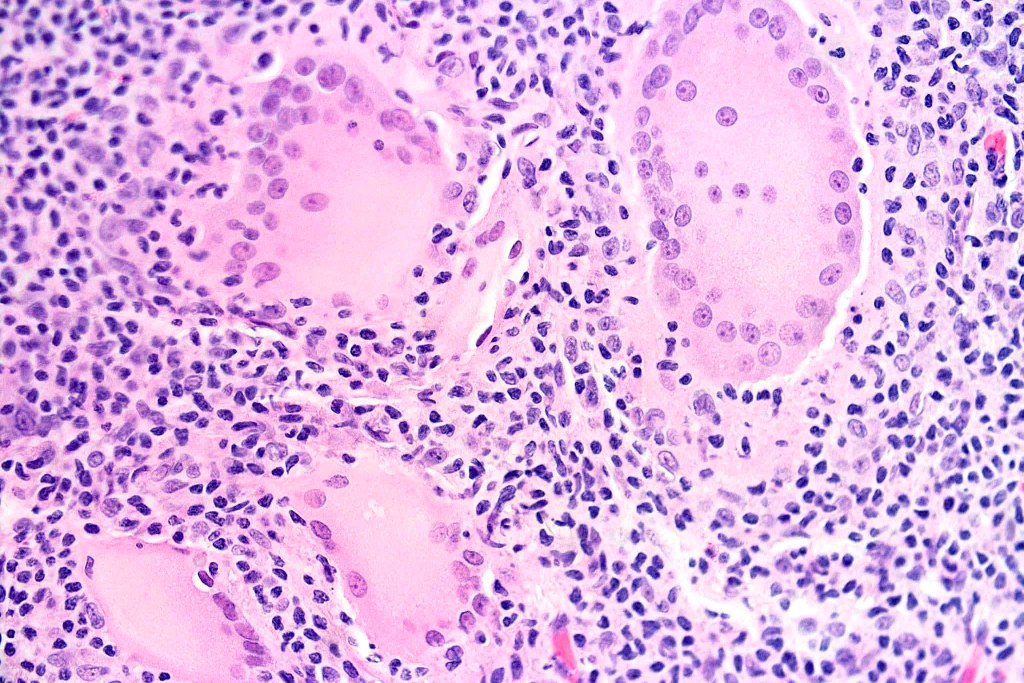

•Established lesions are readily recognizable & characterized by a dense infiltrate throughout the dermis &extending into subcutaneous fat

•Atypical, hyperchromatic lymphocytes, Sezary cells, histiocytes, plasma cells, eosinophils & characteristic multinucleate giant cells (innumerable nuclei resembling a shoal of fish)

•Loss of dermal elastic tissue

Elastophagocytosis, can be subtle and best demonstrated with an elastic tissue stain (in the 6 cases that I have personally observed, elastophagocytosis has not been present)